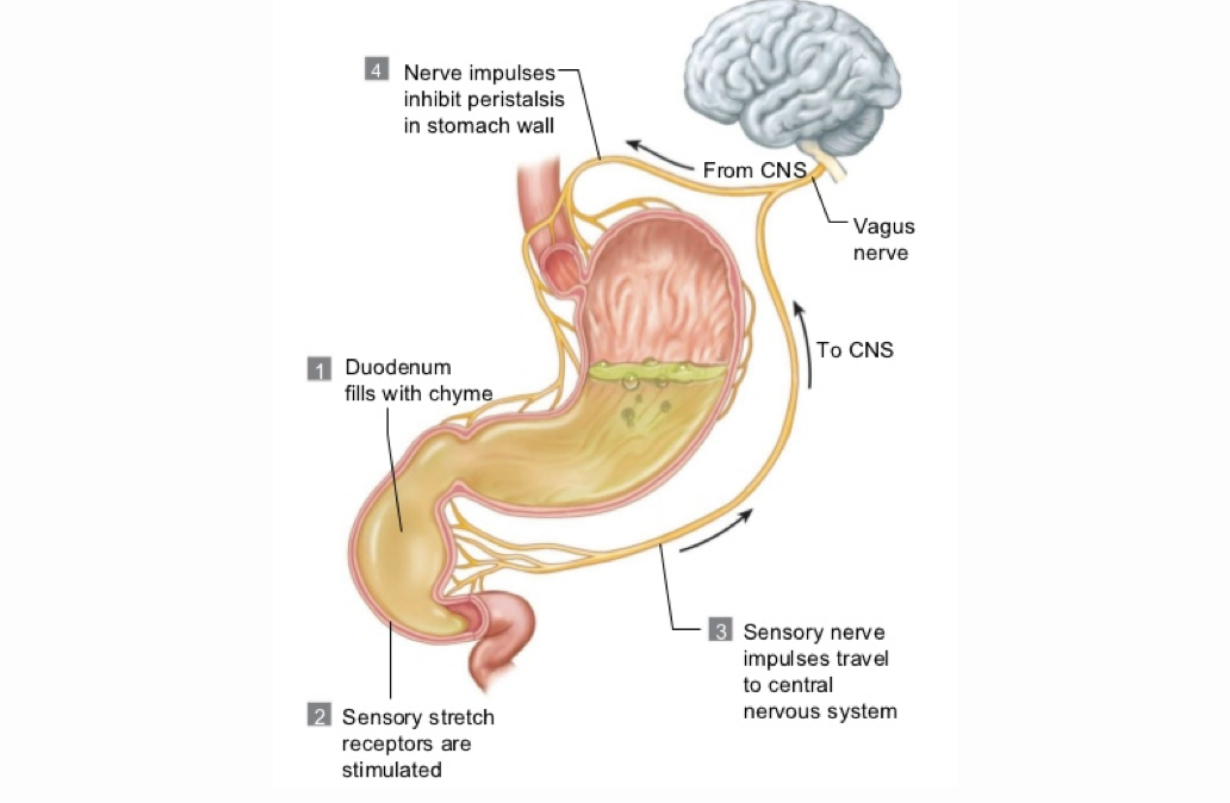

GERD - Gastroesophageal Reflux Disease

Leaking of acidic stomach contents back up into the esophagus, often causing heartburn.